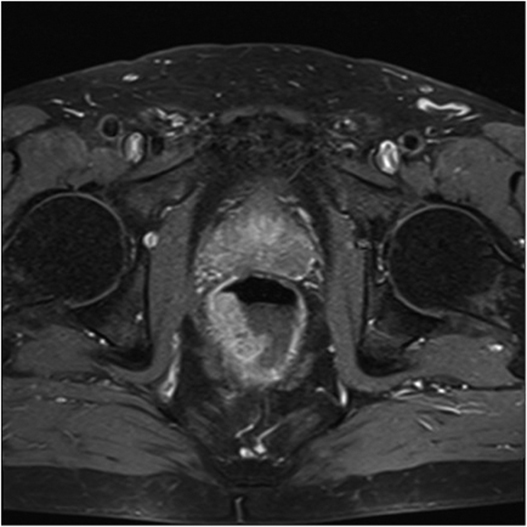

Fig.2. Același pacient post chimio-/ radioterapie – răspuns complet cu dispariția masei tumorale rectale; dispariția restricției de difuzie și reducere în dimensiuni a ganglionilor mezorectali; pacientul a beneficiat de TME şi s-a confirmat histopatologic absenţa ţesutului tumoral (pT0 pN0).

a-d) imagini T2 ponderate în 3 planuri

e) difuzie RM (b1000)

f) sagital T1 postcontrast